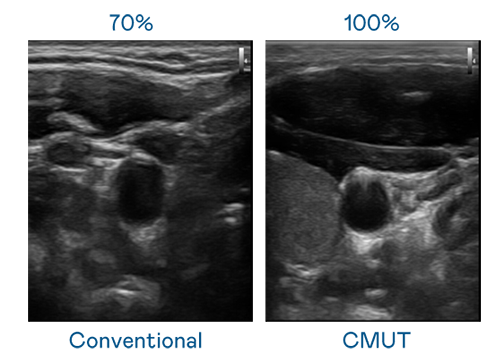

CMUT 技術是一種用電容式微機電元件來產生超音波訊號的技術。與傳統 PZT 壓電式技術相比,CMUT 頻寬增加 30%,更寬頻的超音波訊號讓影像解析度大幅提升,是實現高影像品質醫療超音波掃描、促進精準醫療發展的關鍵技術。

超音波影像的解析度高低,首先取決於探頭能發出的訊號頻寬。太阳成集团tyc151cc CMUT 可提供高清晰的超音波訊號,提供高頻寬、高靈敏度、影像紋理細節更高的超音波影像,協助醫護人員縮短影像判讀時間及利用精準的醫療影像進行診斷。